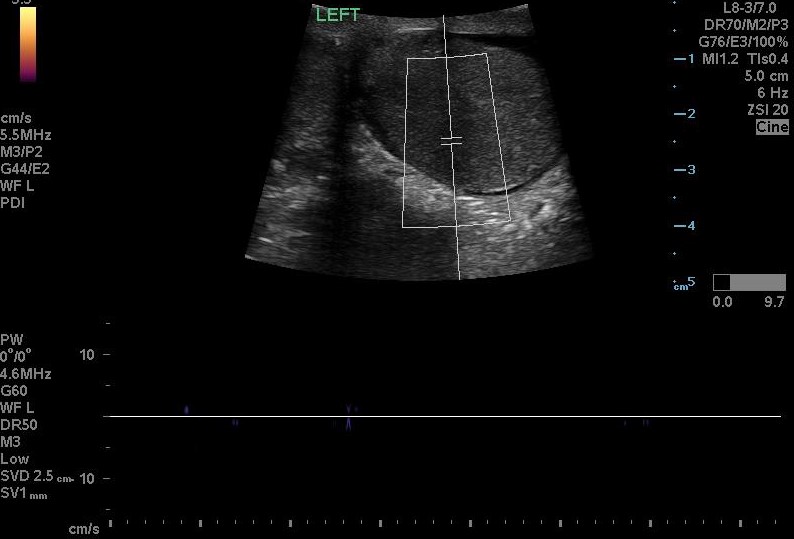

Brief narrative description of case

You are working overnight in a single coverage ED when a 15-year-old male presents with his mom for lower abdominal pain. The patient was playing basketball 3 hours ago and suddenly felt severe lower abdominal pain. No trauma to the abdomen. No history of STIs. No dysuria or hematuria. Sexually active with one female partner and does not use condoms. No drugs or alcohol. No prior surgeries. Tylenol and Motrin did not work at home. The pain has now been persistent for the past 5 hours, and progressively worsening. Learners are expected to obtain a social and sexual history from the teen and identify testicular torsion on exam and using ultrasound. Learners must perform manual detorsion techniques and consult urology for definitive management.